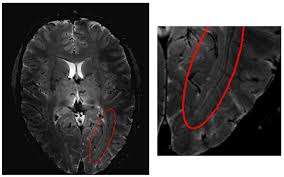

Integrating spatial fuzzy clustering with level set methods for automated medical image segmentation

The performance of the level set segmentation is subject to appropriate initialization and optimal configuration of controlling parameters, which require substantial manual intervention. A new fuzzy level set algorithm is proposed in this paper to facilitate medical image segmentation. It is able to directly evolve from the initial segmentation by spatial fuzzy clustering. The controlling parameters of level set evolution are also estimated from the results of fuzzy clustering. Moreover the fuzzy level set algorithm is enhanced with locally regularized evolution. Such improvements facilitate level set manipulation and lead to more robust segmentation. Performance evaluation of the proposed algorithm was carried on medical images from different modalities. The results confirm its effectiveness for medical image segmentation.